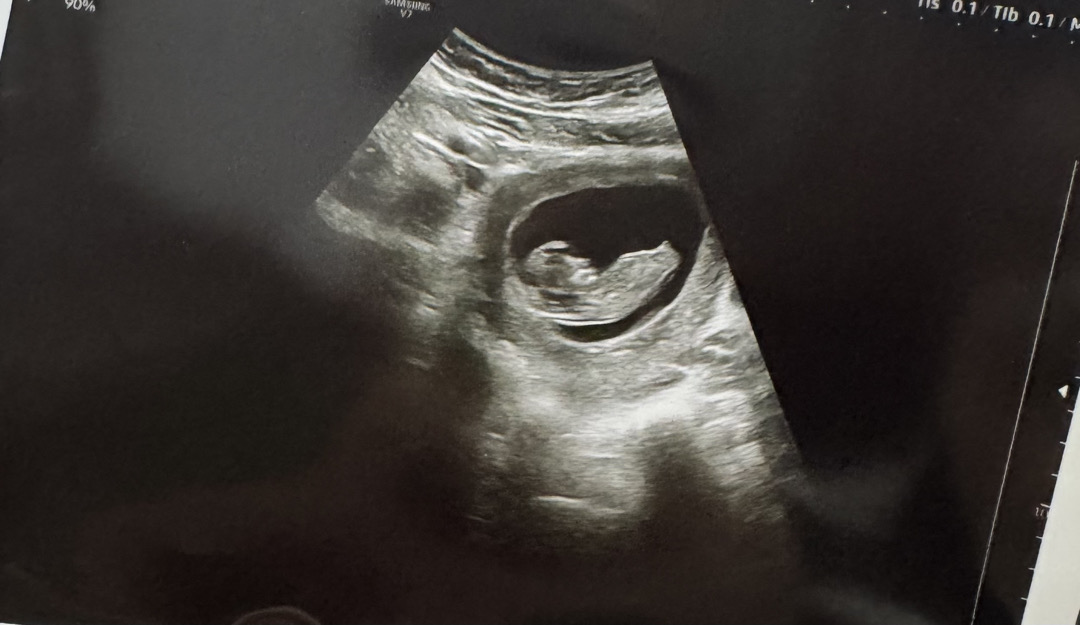

아들같아요~!

각도 고수님들 너무 이르긴한데 한번만 봐주세요!! ㅎㅎㅎ